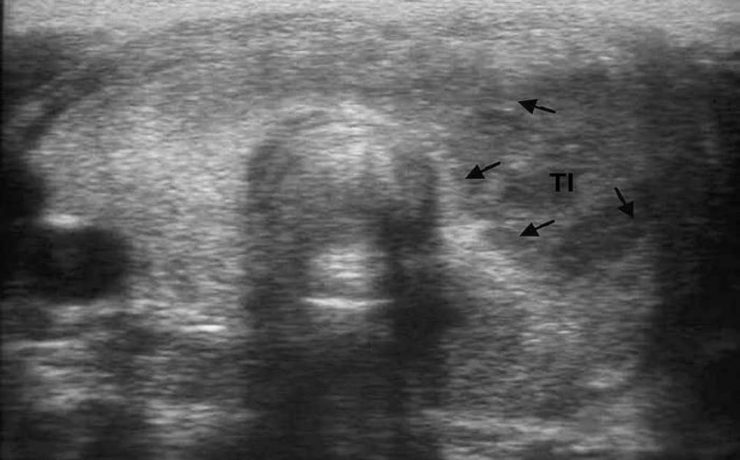

ÚTERO Y OVARIOS Al estudiar el hueco pélvico hay que tener en cuenta la anatomía del sistema reproductor femenino ya que partiendo de esto se podrán identificar anomalías en los mismos. Un punto importante para el estudio del hueco pélvico es utilizar la vejiga urinaria como ventana sónica, sin caer